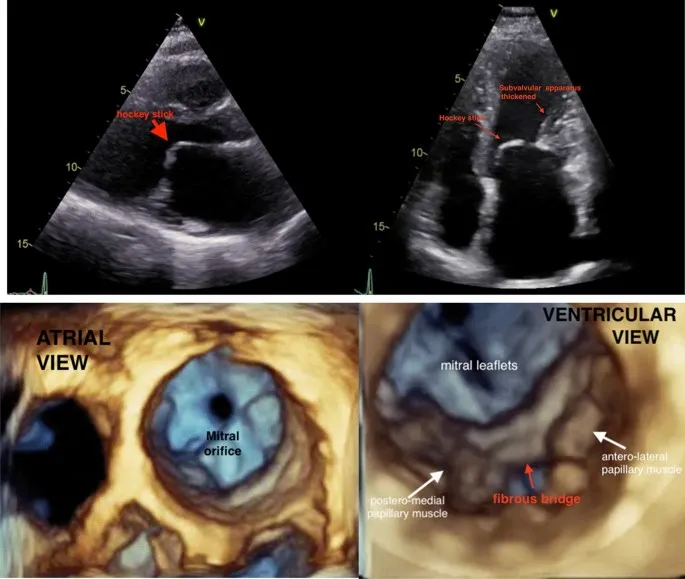

- Echo: MVA < 1.5 cm² (severe < 1.0 cm²); "Hockey-stick" leaflet.